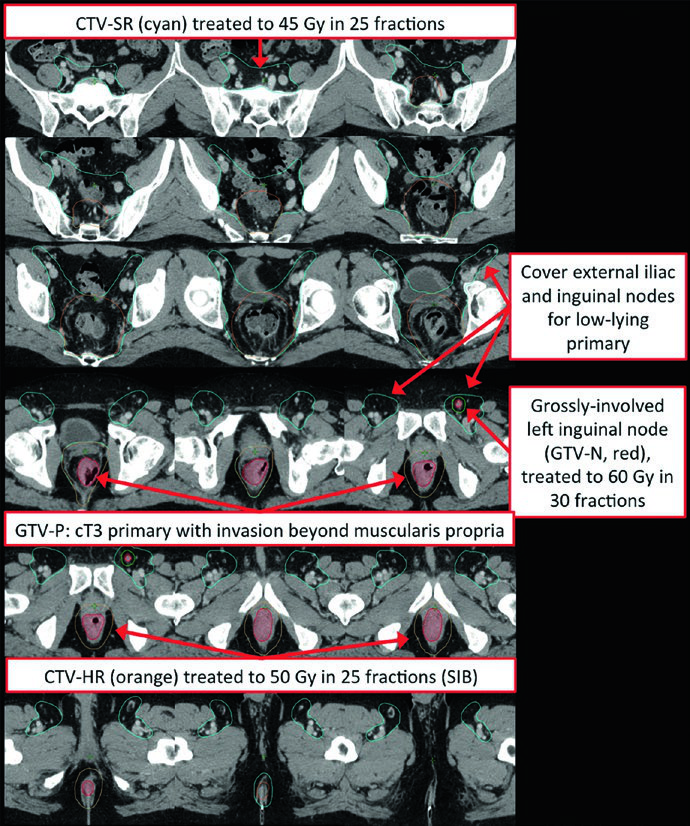

The primary GTV (GTV-P) encompasses all gross disease identified on physical examination, endoscopy, and imaging. The nodal GTV (GTV-N) includes all visible perirectal, mesorectal, and involved iliac lymph nodes. In the absence of biopsy, any lymph node in doubt should be included as GTV. Low-lying rectal tumors require attention to the inguinal nodes, and tumors with anterior invasion into adjacent organs warrant evaluation of external iliac nodes.

The high-risk CTV (CTV-HR) should include the GTV with a minimum 1.5 to 2 cm superior and inferior margin, plus the entire rectum, mesorectum, and presacral space. For grossly involved external iliac or inguinal nodes, the GTV-to-CTV margin should be at least 10 to 15 mm. In T4 tumors, a 1 to 2 cm margin into adjacent invaded organs (bladder, prostate, cervix) is added.

The standard-risk CTV (CTV-SR) covers the entire CTV-HR, mesorectum, and bilateral internal iliac lymph nodes. For T4 tumors with anterior organ involvement (bladder, cervix, prostate), the bilateral external iliac and obturator nodes must be included. If the primary tumor extends into the anal canal, bilateral external iliac and inguinal nodes are added to CTV-SR.

Low-lying rectal tumors involving the anal canal present a distinct challenge. Bilateral inguinal coverage becomes mandatory, and IMRT is typically necessary to achieve adequate conformality covering the external iliac and inguinal nodes bilaterally. The overlap with anal cancer target delineation is significant, since both share many of the same nodal drainage pathways.

Multiple acceptable approaches exist for dose prescription in rectal cancer. In the preoperative setting, the most common scheme is 45 Gy at 1.8 Gy per fraction to the PTV-SR, followed by a sequential cone-down boost of 5.4 Gy at 1.8 Gy per fraction, totaling 50.4 Gy to the PTV-HR. Clinical T4 tumors may receive a PTV-HR boost to 54-55.8 Gy in 30-31 fractions. Grossly involved lymph nodes not planned for resection (e.g., inguinal) should be boosted to approximately 60 Gy in 30 fractions, while nodes that will be resected can be treated to 50.4 Gy.